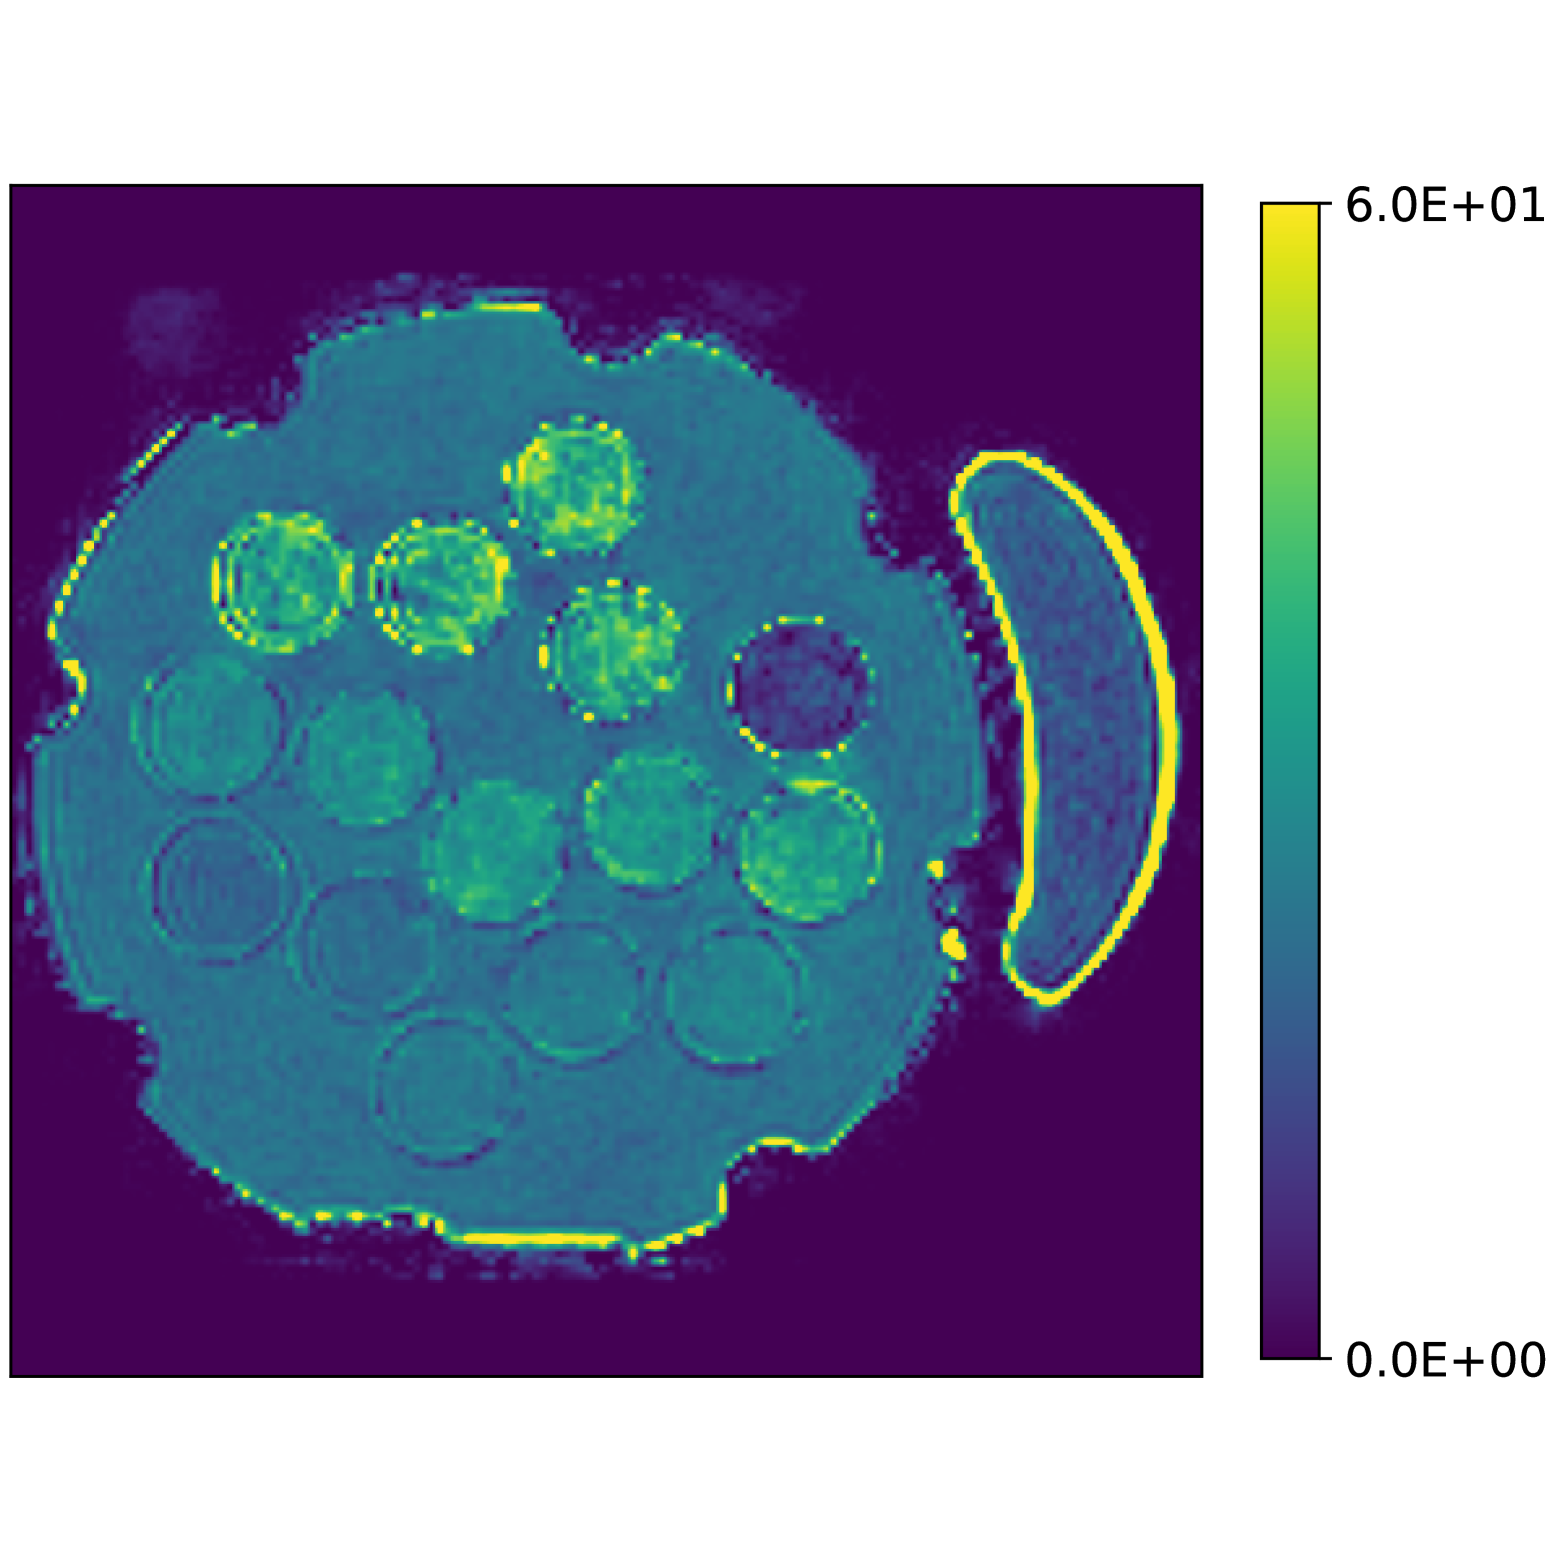

In Figs. 2(f), 2(g) and 2(h) show the recovered concentrations of water, fat and silicone, and Fig. 2(j) shows the recovered . These recovered quantities are all qualitatively similar to their true values. In contrast, Fig. 2(i) shows the recovered fieldmap, which differs from its true value. By comparing the errors in the recovered concentrations, we see that they are within a reasonable accuracy except in regions with a large magnitude for the fieldmap gradient, indicating a bound that is too small (Figs. 2(k), 2(l) and 2(m)). A similar behavior is seen in the recovered (Fig. 2(o)). The error for the recovered fieldmap tends to be larger outside the area of the phantom (Fig. 2(n)).

To reconstruct the concentrations and the parameters, we used a bound on the magnitude of the gradient of Hz at voxels with signal magnitude above 10% of the maximum value of the signal accross the entire field of view.

Figs. 3(a), 3(b) and 3(c) show the recovered concentrations of water, fat and silicone, and Figs. 3(e) and 3(f) show the recovered fieldmap and . Fig. 4 shows the error of the recovered Proton Density Fat Fraction (PDFF) compared to the reference values obtained using Magnetic Resonance Spectroscopy (MRS-PDFF). Table 2 details the PDFF measurements in each vial.